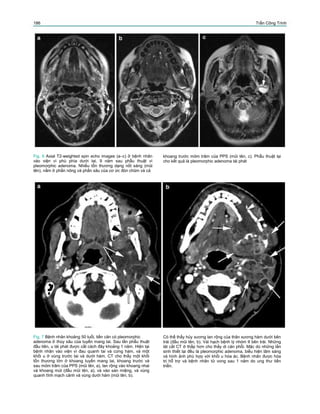

Fig. 4 Axial T2-weighted (a) và gadolinium-enhanced T1-

trước trong của u (đầu mũi tên đen ở b).

Thành của hầu (đầu mũi tên trắng) và cơ chân bướm trong

(mũi tên trắng) bị đẩy lệch. Những mạch máu lớn (mũi tên

cong) bị đẩy ra sau. Mỏm trâm và các cơ của mỏm trâm ấn lõm

bờ sau của khối u (đầu mũi tên đen, ở a). Pleomorphic

adenoma của thùy sâu tuyến mang tai.

Dấu hiệu đáng tin nhất của một khối u nguyên

phát thuộc PPS là sự hiện diện lớp mỡ ngăn cách

khối u với thùy sâu của tuyến. Khối u xuất phát từ

thùy sâu của tuyến mang tai có dạng quả tạ đôi, nối

với tuyến mang tai, có khả năng mở rộng ống mỏm

trâm – hàm dưới, và di lệch lớp mỡ của PPS ra

trước – vào trong (Fig. 4). Fig. 5 Axial plain T1-weighted spin echo ở bệnh nhân phù quanh